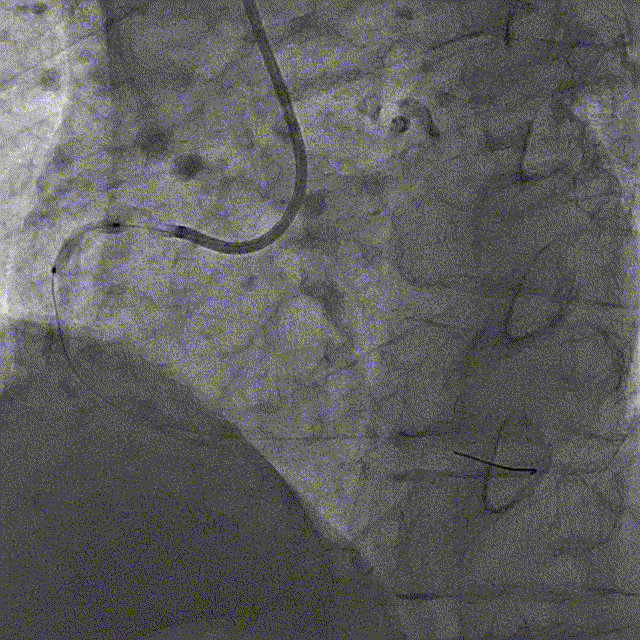

冠脉内介入治疗